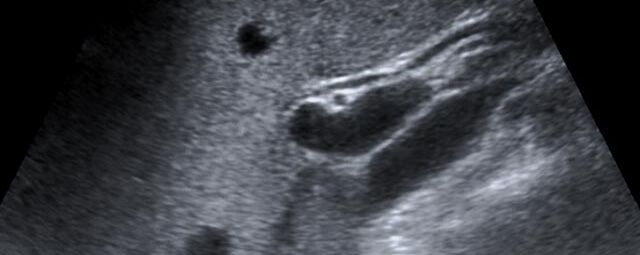

Die Sonographie ist ein bildgebendes Verfahren in der medizinischen Diagnostik, das mit Ultraschallwellen arbeitet. Ultraschall ist Schall mit einer Frequenz oberhalb der menschlichen Hörgrenze. Im medizinischen Bereich werden je nach Körperregion Ultraschallwellen in einem Frequenzbereich von ca. 3,5 – 18 Mhz verwendet. Die körpernahe Ultraschallsonde sendet durch einen piezoelektrischen Effekt kurze Schallwellenimpulse in den Körper. Ultraschall-Gel stellt den Kontakt zwischen Sonde und Körper her. Je nach Gewebeart werden diese Schallwellen im Körper unterschiedlich stark reflektiert. Anhand des zurückgesendeten Schallmusters kann das Ultraschallgerät Schnittbilder berechnen, auf denen die Organe des Körpers nach krankhaften Veränderungen untersucht werden können.